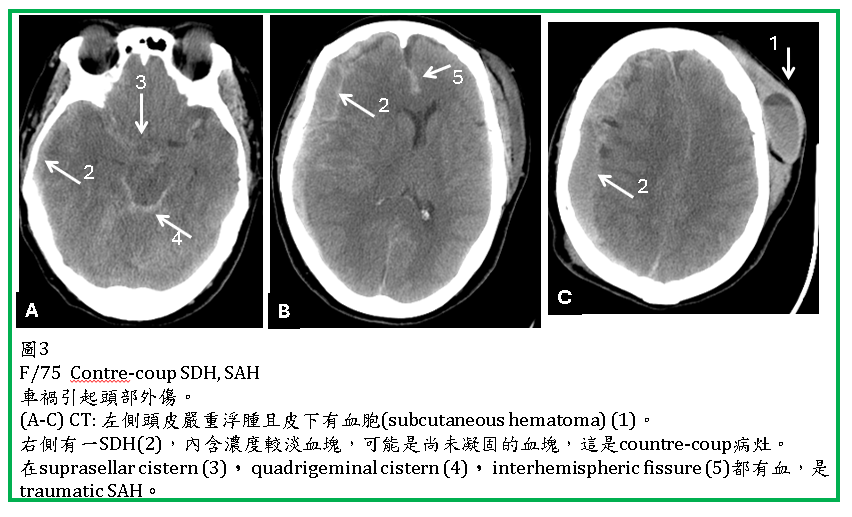

外傷性SAH (Traumatic SAH)

外傷性蜘蛛網膜下腔出血(traumatic subarachnoid hemorrhage, SAH) 很常見,可以單獨發生,但更常合併brain contusion, SDH, EDH。

Traumatic SAH 於CT上常見於大腦腦溝(sulcus),腦裂(Sylvian fissure, interhemispheric fissure),腦池(如suprasellar cistern),以及小腦天幕旁 (tentorial edge)。CT對於SAH及IVH的診斷很敏銳,但在成年人interhemispheric fissures內的falx鈣化與SAH容易混淆。位於tentorium edge 以及interhemispheric fissures內的SAH,與SDH不易區分,coronal reconstruction 有助於鑑別。